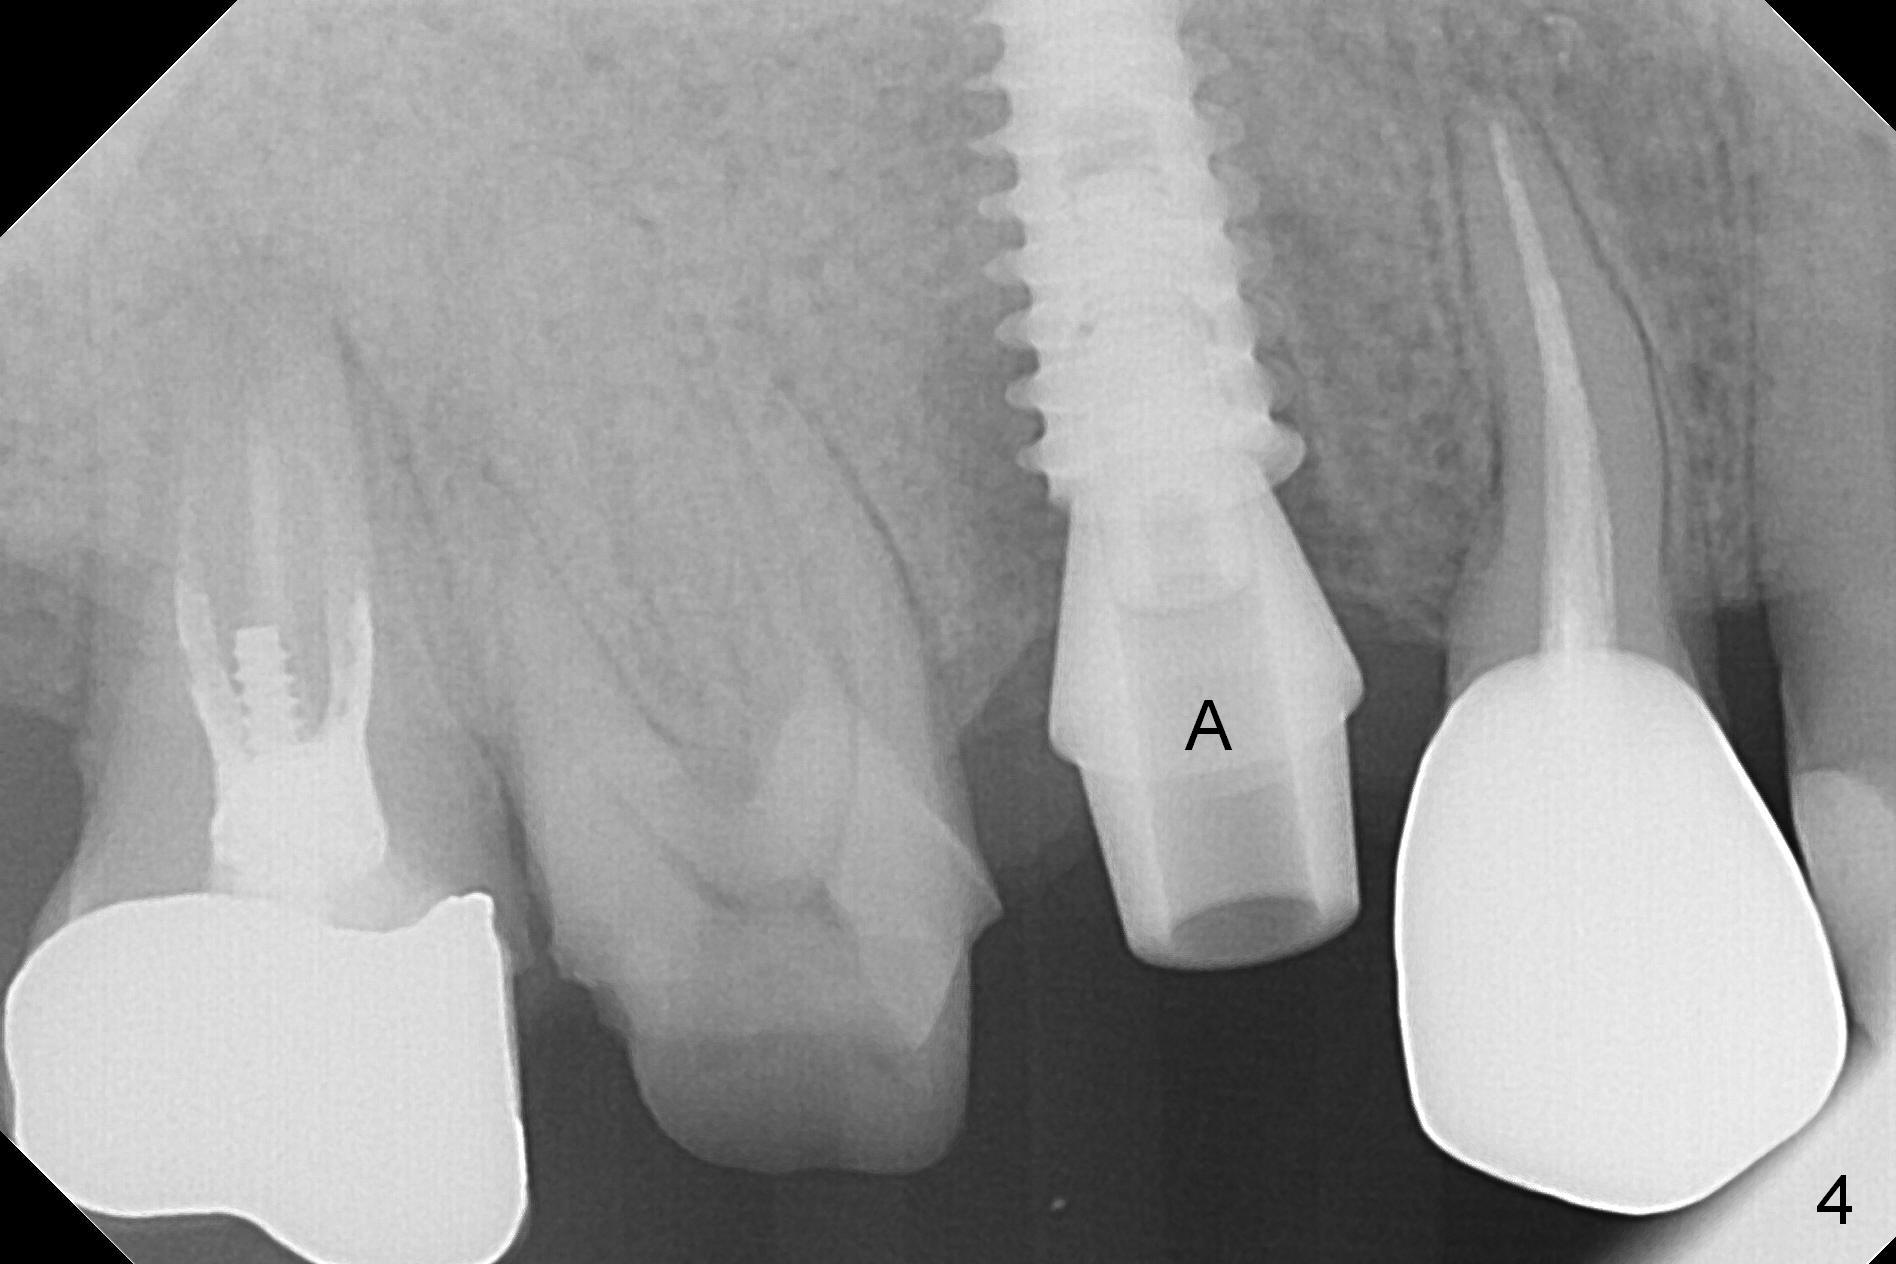

When the tooth #4 with vertical root fracture is extracted, the socket is large, approximately 6x10x10 mm (Fig.1 (mesiodistal x buccopalatal width x depth)). Osteotomy is established in the middle of the socket with 2 mm initial drill for 7 mm, 2.8 and 3.6 mm rounds drills (from DIO Sinus Master Kit) for < 7 mm, and 3.0 and 3.8 mm Magic Expanders. A 4x11 mm dummy implant is placed with insertion torque of 30 Ncm (Fig.2,3 (^: sinus floor)). There is a gap between the socket wall and the implant (*). To reduce the gap and periimplantitis, a 5x11 mm IBS implant is placed with insertion torque > 50 Ncm after further osteotomy using Magic Drills (Fig.4,5). Following placement of 5.5x4(4) mm abutment (A) and bone graft (data not shown), a splinted provisional is fabricated at #3 and 4. The provisional is stable 3 months postop (Fig.6,7). The peri-implant gaps (Fig.4,5) seem to disappear (Fig.6) with the help of bone graft. Bone graft appears to remain between the implant fins (Fig.7 arrows). Impression is taken 4.5 months postop (Fig.8,9). The abutment dislodges 4 months post cementation. After retightening, there is clearance for shim after use of 2 layers of thick articulating paper. Is the abutment screw too short? Or Titanium V is too hard for welding? The abutment/crown dislodges again 1 year 3 month post cementation; it appears that the fact that the implant is placed deep contributes to abutment screw loosening (Fig.10,11). An abutment screw will be buried inside the implant well 10 days post initial retightening.